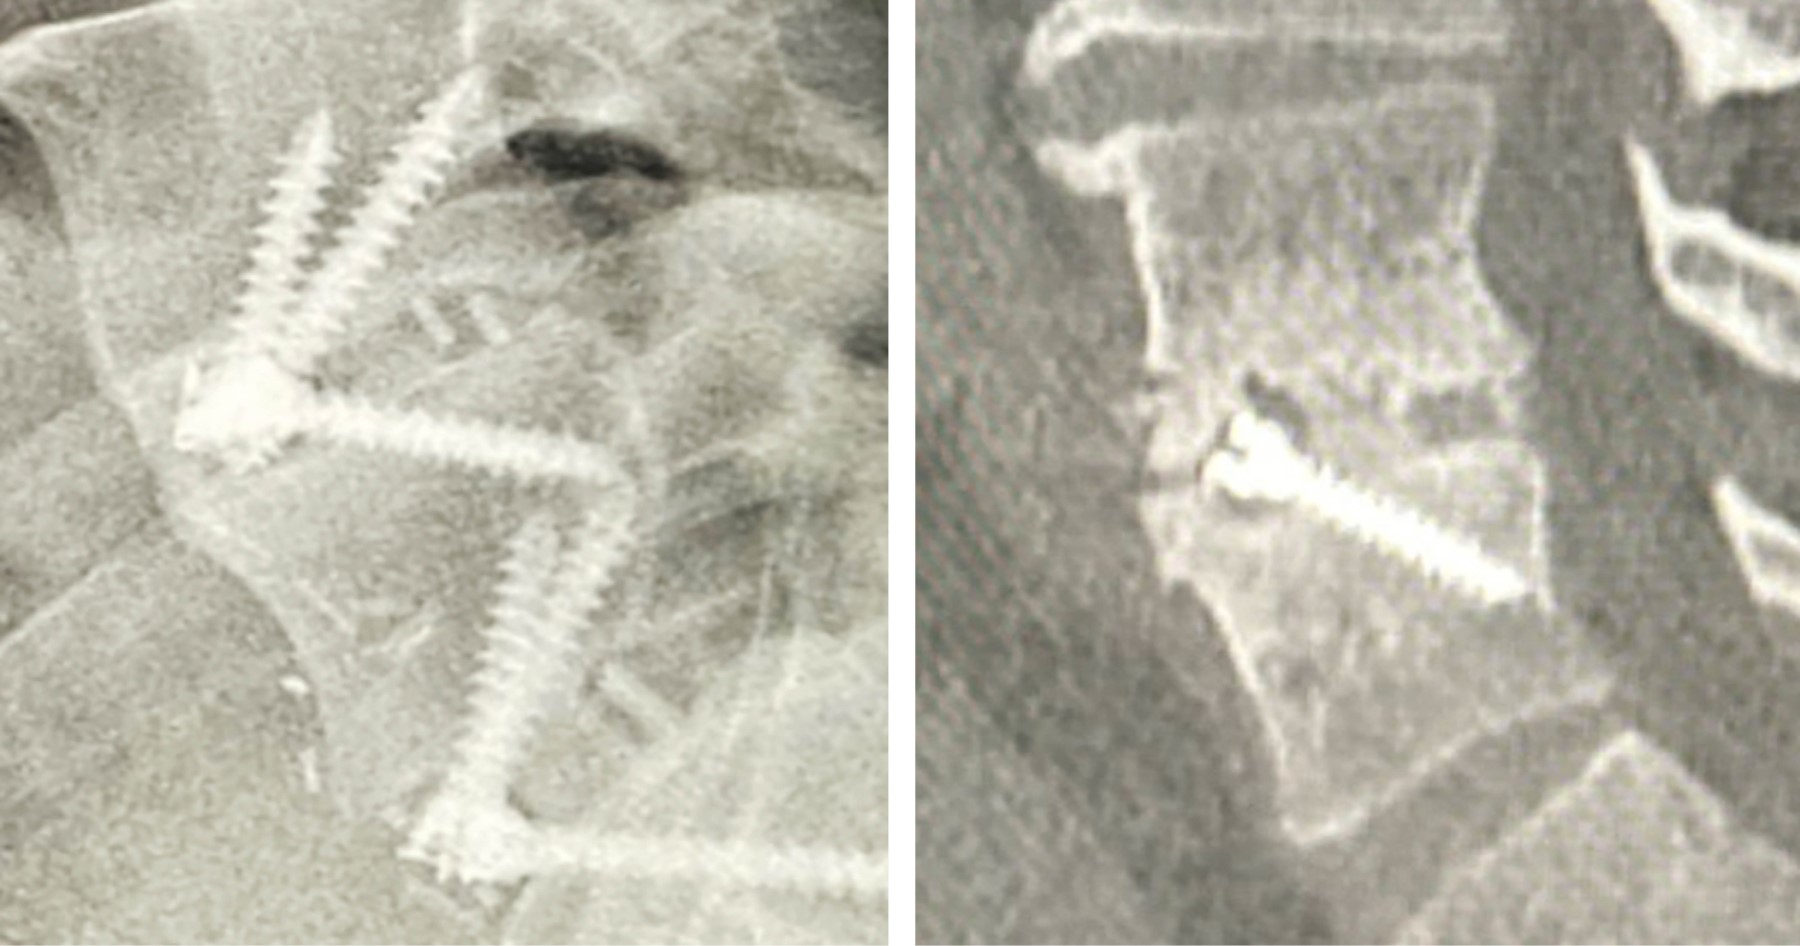

Fusión: Cincuenta y tres (96.36%) niveles presentaron fusión evidente por estudio de imagen a los seis meses de seguimiento (Figura 1).